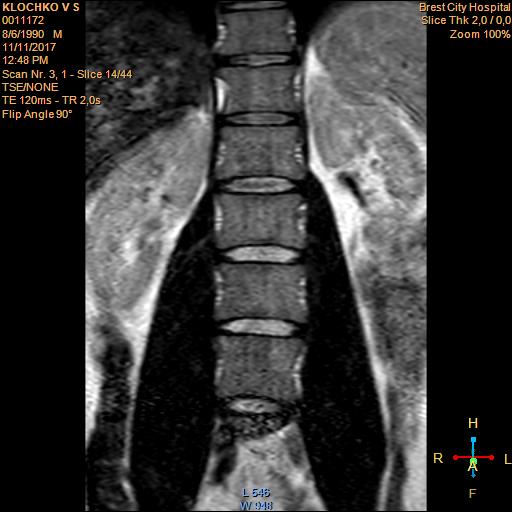

Тренировки с межпозвоночной грыжей.